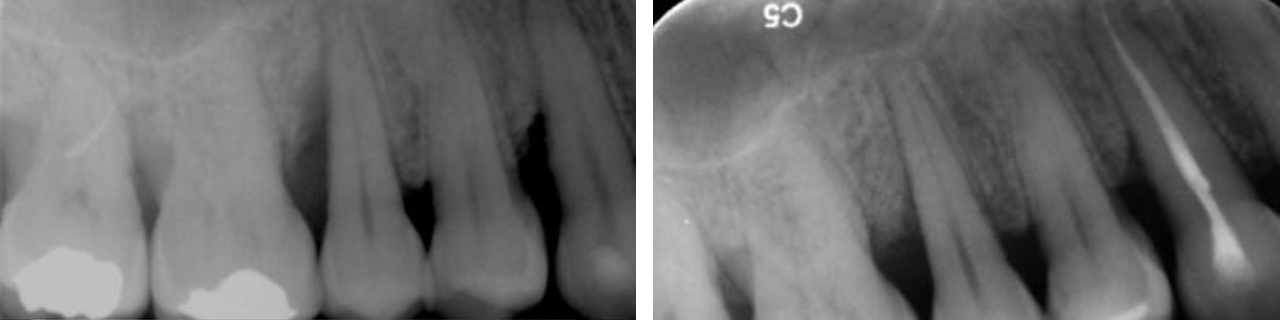

Regeneración del hueso alrededor de los dientes.

Regeneración del soporte dental.